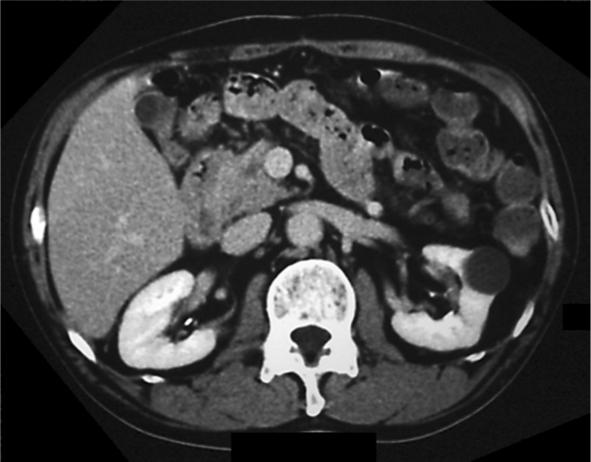

A 61-year-old man was admitted to our hospital with epigastric pain and vomiting. Enhanced abdominal computed tomography revealed inflammatory change of the pancreatic groove and focal wall thickening of the second portion of the duodenum with several cystic lesions around the head of the pancreas. We diagnosed atypical type of groove pancreatitis. The patient made a satisfactory recovery by conservative medication treatment for acute on chronic pancreatitis and cystic lesions disappeared in parallel with pancreatitis. Groove pancreatitis is a rare form of chronic pancreatitis, and to the best of our knowledge, our patient is the first case in the English literature of groove pancreatitis with cystic lesions around the head of the pancreas, which disappeared after conservative treatment for pancreatitis.

摘要

一名61岁男性因上腹部疼痛和呕吐入院。腹部增强计算机断层扫描显示胰沟有炎症改变,十二指肠第二部局部肠壁增厚,胰腺头部周围有多个囊性病变。我们诊断为非典型性胰沟炎。通过对慢性胰腺炎急性发作和囊性病变进行保守药物治疗,患者恢复良好,囊性病变与胰腺炎同时消失。胰沟炎是一种罕见的慢性胰腺炎形式,据我们所知,我们的患者是英文文献中首例胰腺头部周围有囊性病变的胰沟炎患者,经胰腺炎保守治疗后囊性病变消失。